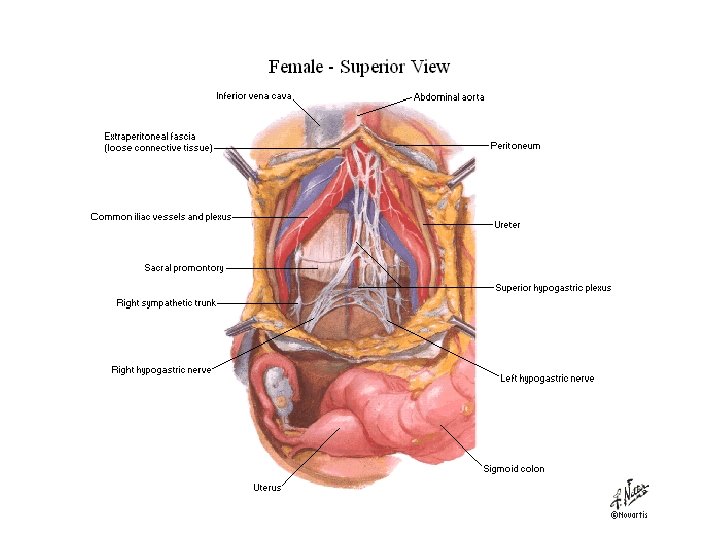

Pelvic Autonomics • Superior hypogastric plexus (presacral nerve) – Contains no parasympathetics • Hypogastric nerve • Inferior hypogastric plexus – Contains parasympathetic fibers from the pelvic splanchnics • Ganglion impar

Pelvik Organların Sinirleri

Pelvik Organların Sinirleri